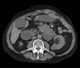

Emphysematous gastritis